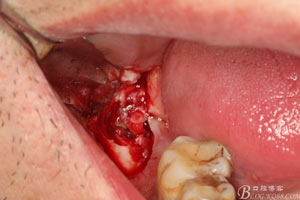

圖9.高速牙鉆分牙:

圖10.先頰舌向橫斷、然后再把牙冠近遠(yuǎn)中向縱分

圖11. “T”型的分牙。

圖12. 先取出48牙冠